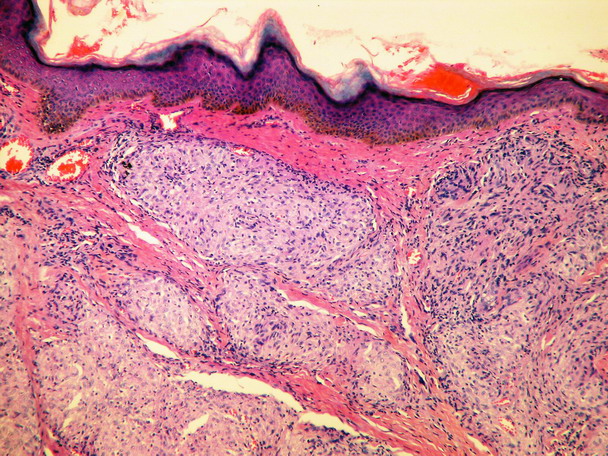

Histology[edit | edit source]

Sharply demarcated circular non-caseifying granulomas. Composed of epithelioid macrophages (histiocytes), surrounded by a negligible lymphocyte infiltrate. They are therefore referred to as "naked".